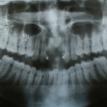

DENTAL IMPLANTS

DENTAL AESTHETICS

- dental implants

- SERVICES